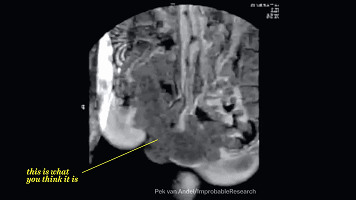

第5是什么,看不懂